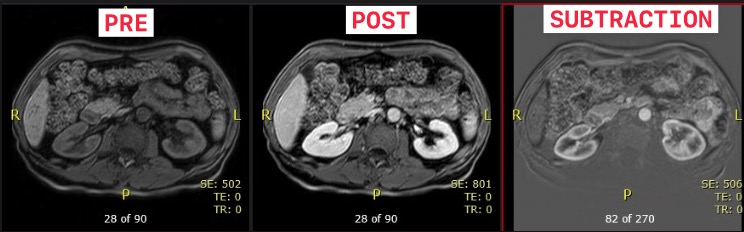

MRI Abd Pre Post Subtraction

Please check images to ensure contrast is present and subtractions have been generated. Manually generate subtractions if needed.